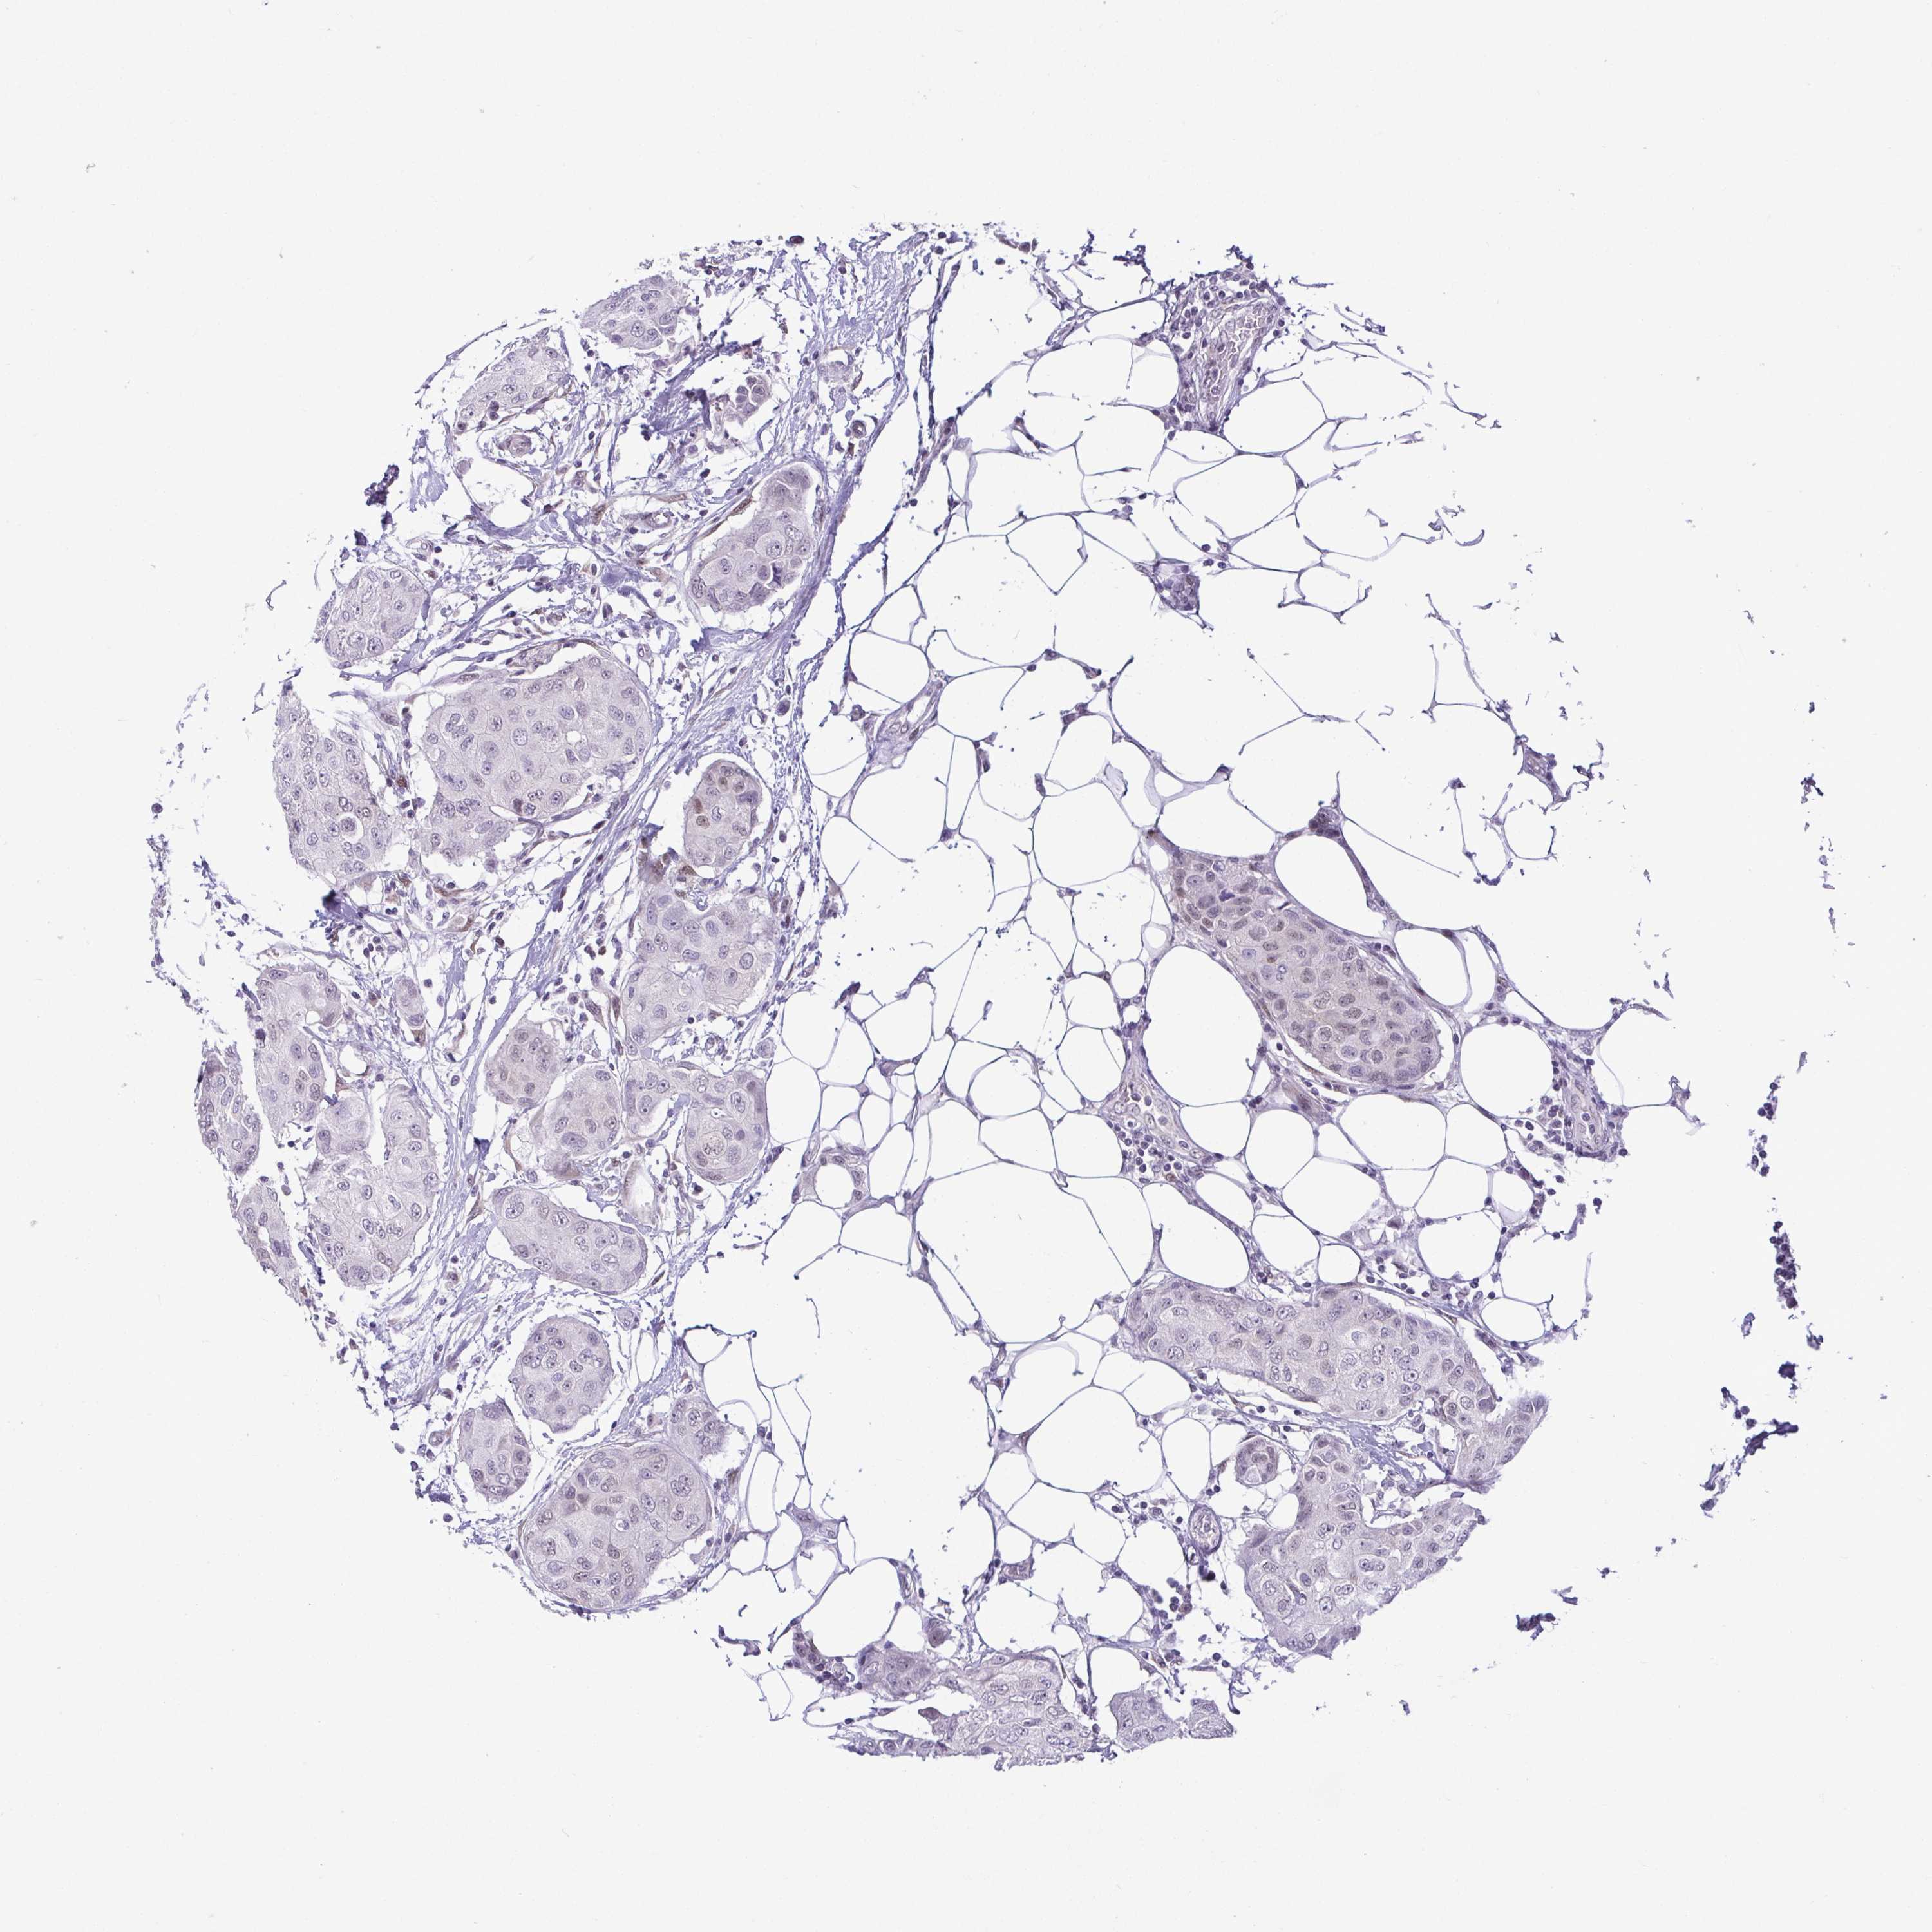

CANCER BREAST CANCER Show tissue menu

BRCA TCGA BRCA VALIDATION PROTEIN EXPRESSION

ANTIBODIES

AND

VALIDATION